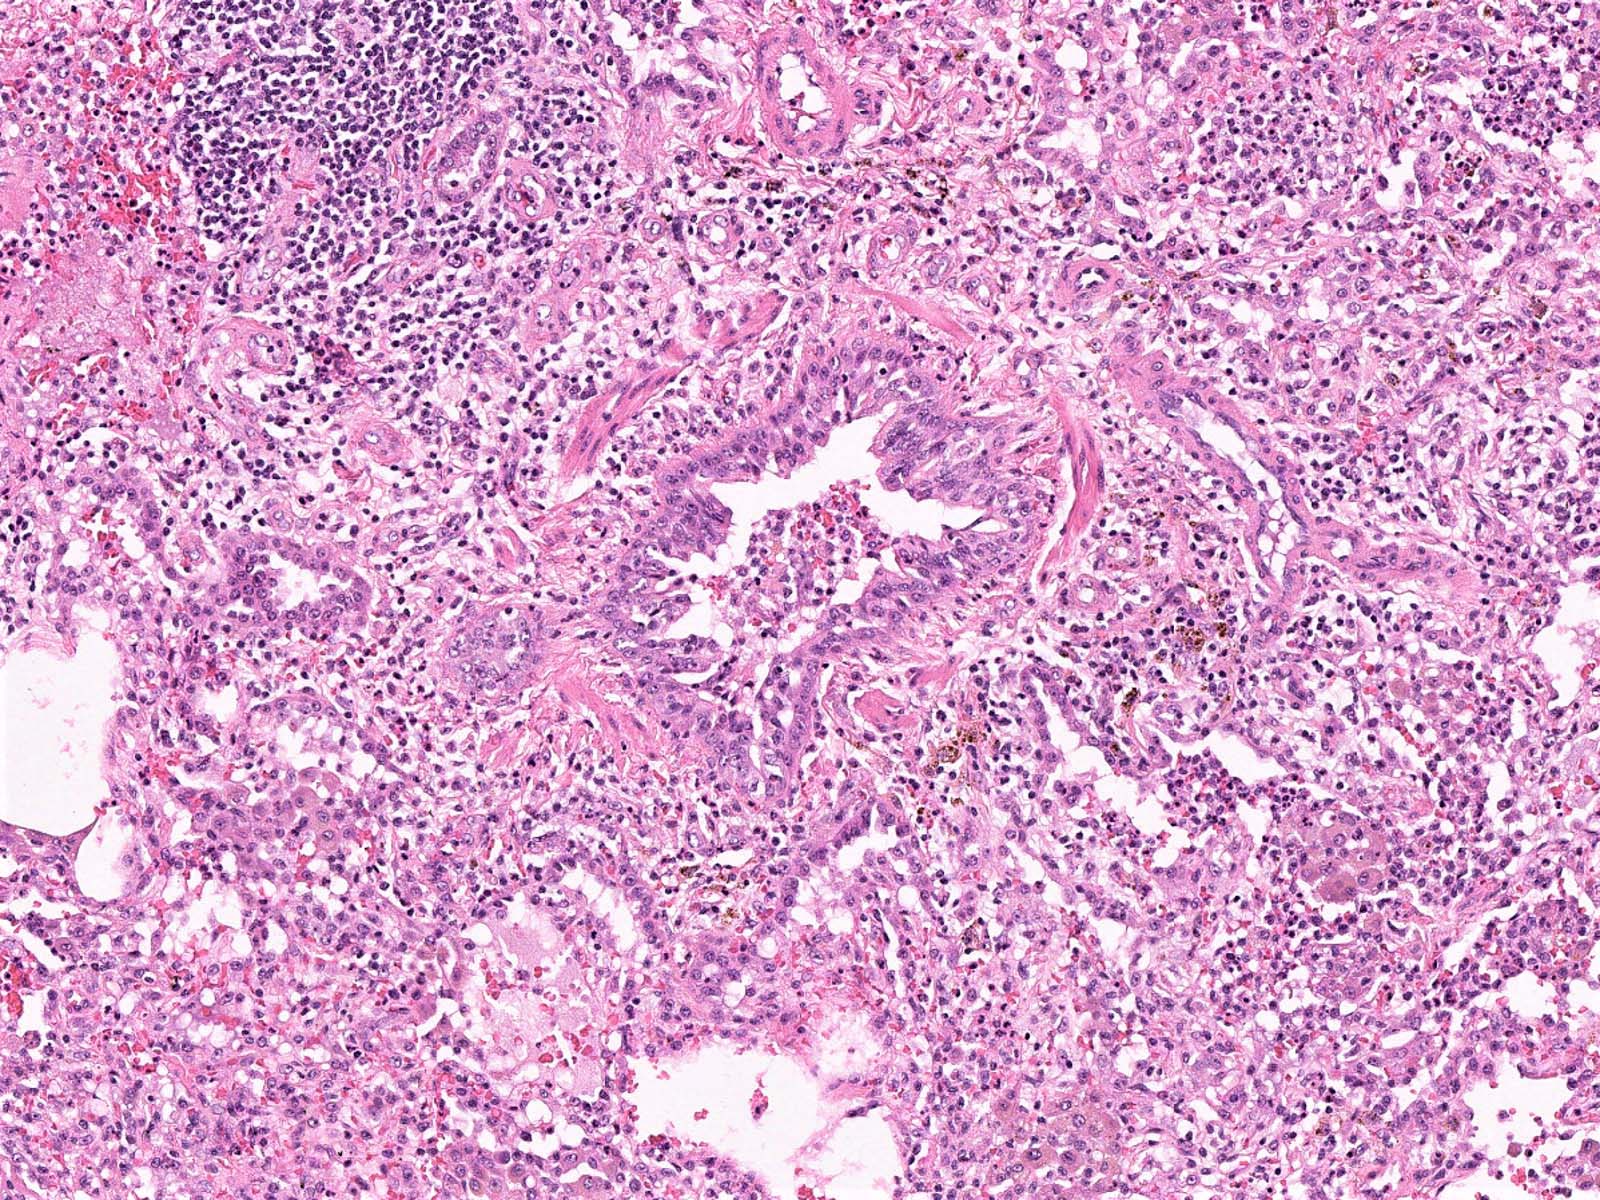

Microscopic (histologic) description

- Bronchopneumonia:

- Most common pattern of pulmonary infection

- Different stages in the different areas

- Patchy intra-alveolar fibrinopurulent exudate with neutrophils

- Necrotizing pneumonia (Can Respir J 2014;21:239):

- Characterized by necrotizing inflammation, leading to alveolar septa disruption and cavity formation

- Common organisms: Staphylococcus aureus, Streptococcus pyogenes, S. pneumoniae (certain serotypes), Klebsiella, Acinetobacter, Pseudomonas and Burkhodoria

Microscopic (histologic) images